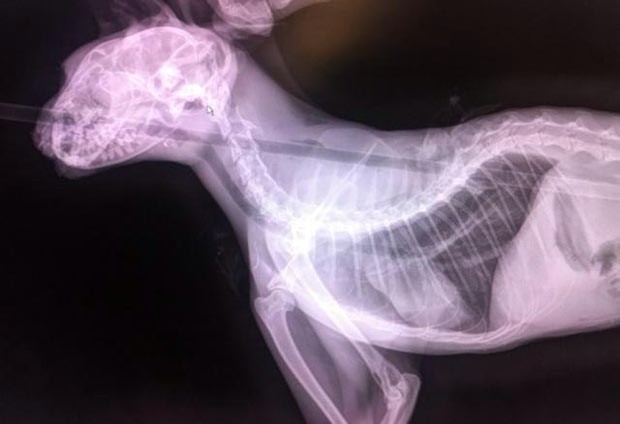

Raio-X mostra a flecha que atingiu o gato Quiver | Foto: Reprodução/Internet

A flecha entrou pela cabeça, atravessou o esôfago e saiu pelas omoplatas do animal, segundo funcionários da ONG One More Chance C.A.T.S.